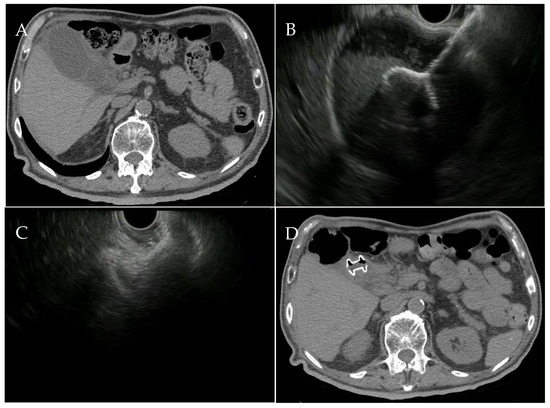

3. EUS-Guided Gallbladder Drainage: Technical Aspects

- Law, R.; Grimm, I.S.; Stavas, J.M.; Baron, T.H. Conversion of Percutaneous Cholecystostomy to Internal Transmural Gallbladder Drainage Using an Endoscopic Ultrasound-Guided, Lumen-Apposing Metal Stent. Clin. Gastroenterol. Hepatol. 2016, 14, 476–480. [Google Scholar] [CrossRef] [PubMed]

- Chantarojanasiri, T.; Matsubara, S.; Isayama, H.; Nakai, Y.; Takahara, N.; Mizuno, S.; Kogure, H.; Hakuta, R.; Ito, Y.; Tada, M.; et al. Feasibility of conversion of percutaneous cholecystostomy to internal transmural endoscopic ultrasound-guided gallbladder drainage. Saudi J. Gastroenterol. 2017, 23, 318–322. [Google Scholar] [CrossRef] [PubMed]

- Minaga, K.; Yamashita, Y.; Ogura, T.; Takenaka, M.; Shimokawa, Y.; Hisa, T.; Itonaga, M.; Kato, H.; Nishikiori, H.; Okuda, A.; et al. Clinical efficacy and safety of endoscopic ultrasound-guided gallbladder drainage replacement of percutaneous drainage: A multicenter retrospective study. Dig. Endosc. 2019, 31, 180–187. [Google Scholar] [CrossRef] [PubMed]